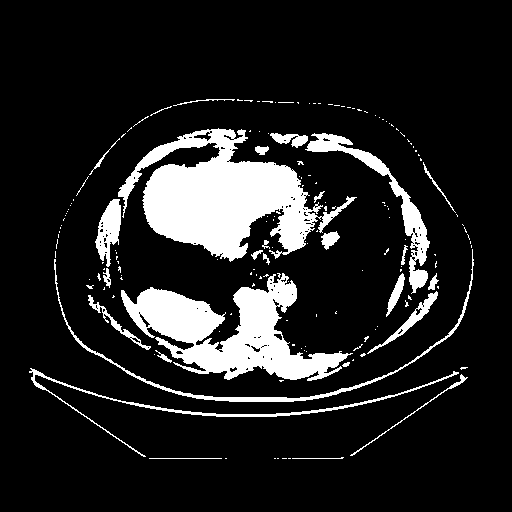

Original NATIVE CT scan (input)

Full window (WL 1023.5, WW 4095 β†’ Low βˆ’1024, High +3071)

Actual HU range: [-1024.0, 3071.0]